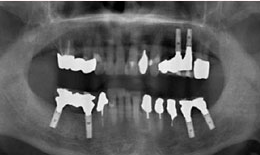

インプラント症例(21)75歳 男性

治療前

上顎

インプラントを2本埋め込んで、セラミックスクラウンを被せた

下顎

インプラントを4本埋め込んで、セラミックスクラウンを被せた